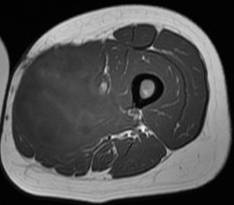

Histiocytofibrome malin. Noter l’aspect hétérogène en T2, avec prise de contraste hétérogène

Histiocytofibrome malin